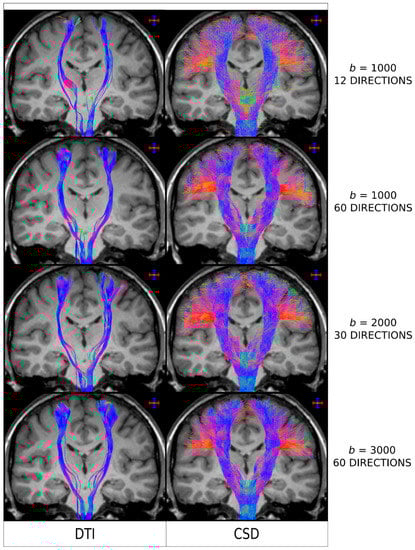

As it is the case with other MRI analysis methods, the better the acquired diffusion MRI data, the better the fibre-tracking results will be. When it comes to diffusion MRI data, two specific parameters have a major impact on the outcome results: the b-value (which determines the degree of diffusion weighted sensitisation), and the number of diffusion-weighted encoding directions. Both parameters have been shown, for example, to influence the achievable angular resolution of the resulting FOD [28]. In particular, if the b-value is too low and/or the number of directions too few (such as it was the case for early DTI protocols, e.g., with 10–20 directions a b-value < 1000 s/mm2), then the reconstructed FODs will be very broad [21,28], in turn leading to greater spread of the fibre-tracking results, lower power to resolve crossing fibres, and noisier streamlines when using a probabilistic fibre-tracking approach [13,30]. This is illustrated in Figure 4, where it can be seen that the choice of b-value and number of directions has a major impact in the quality of the tracking results Interestingly, the tracking results from Figure 4 (and the results shown in more detail in reference [30]), demonstrated that even for data acquired from protocols that could be considered highly unsuitable for higher-order models (e.g. only 12 directions and b = 1000 s/mm2—top row in Figure 4) and, thus, expected to highly favour DTI-based analysis, CSD-based results were still superior to DTI-based results: CSD-based analysis was able to reconstruct lateral projections successfully (albeit more noisier than with a HARDI type acquisition), while these were not reconstructed using DTI.

Figure 4.

Fibre-tracking results on a healthy human subject obtained using a seed region in the brainstem and target regions in the sensorimotor cortices. Coronal T1-weighted images overlaid with tractography results using DTI combined with a deterministic algorithm (left column) and CSD combined with a probabilistic algorithm (right column), for a range of diffusion MRI protocols (as indicated by the b-value, in s/mm2, and number of directions). The colour-coding indicates the fibre orientation (same convention as in Figure 2). DTI: Diffusion Tensor Imaging; CSD: constrained spherical deconvolution. As clarified for the interpretation of the results from Figure 3, and based on the results reported in Figure 2, the general conclusions from this figure are also expected to be applicable to the case of combining DTI with probabilistic tracking. Figure modified from a figure previously published in [30], with permission of American Association of Neurological Surgeons, 2013.

The optimal acquisition protocol can depend on the model used to analyse the data. For example, for the commonly used spherical deconvolution approach, Tournier et al. [44] demonstrated that b-value ~3000 s/mm2 provides the optimal angular resolution for typical acquisition protocols in clinical scanners; for this b-value, it was also shown that a minimum of 45 gradient directions is required. So, while the analysis of retrospective data might need to accept compromises in data quality (e.g., data were acquired before the requirements for the more advanced models have been characterised), it is important that protocols for prospective data acquisition are now carefully tailored to the intended analysis. If structural connectivity based on streamlines tracking is the ultimate aim, a protocol with high angular resolution (often referred to as High Angular Resolution Diffusion Imaging, or HARDI) should be employed, and the b-value must be optimally chosen for the advanced model to be used (e.g., b-value ~3000 s/mm2 for spherical deconvolution analysis). Otherwise, the resulting sub-optimal data quality will have a major impact on the reliability of the tracking results.